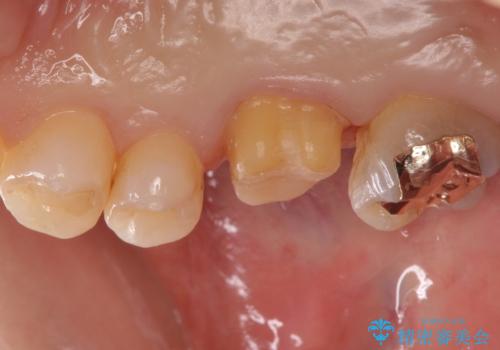

- 奥歯の劣化・変色した樹脂の詰め物をやり直していきます。

セラミックのインレーでは強度に不安が残るため、セラミッククラウンで全体を被覆することとしました。

- 右上6:仮歯+ジルコニアクラウン/11,000円+110,000円費用は治療当時の料金となります